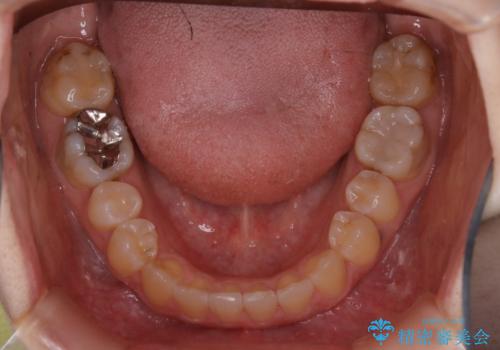

- 受け口で、前歯の嚙み合わせが気になるとの事でご相談にいらした方です。先天的に右上犬歯がなく、左上犬歯も小さい状態でした。矯正治療にて周囲の歯を動かして歯のスペースを確保した上で、被せものにて歯を作っていきました。

歯科技工士さんの熟練した技術により、周囲の歯としっかりなじむ天然歯のような被せ物をお作りすることが出来ました。

矯正治療と補綴治療をうまく組み合わせることで、美しい口元に仕上げることが出来ました。矯正治療、補綴治療をまとめて行える総合歯科治療を体現した治療といえます。